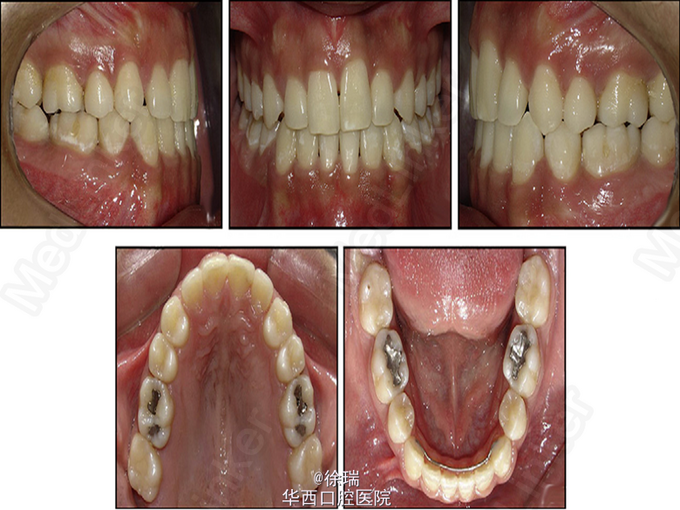

尖牙的异位萌出多见于上颌,可造成相邻牙齿的根尖吸收。最近遇到了一个病例,15岁的女孩儿,安氏III类,上颌尖牙阻生,因为尖牙的位置太过靠近侧切牙和中切牙根方,邻牙发生了严重的根尖吸收。那这样的病情又该如何矫正呢?